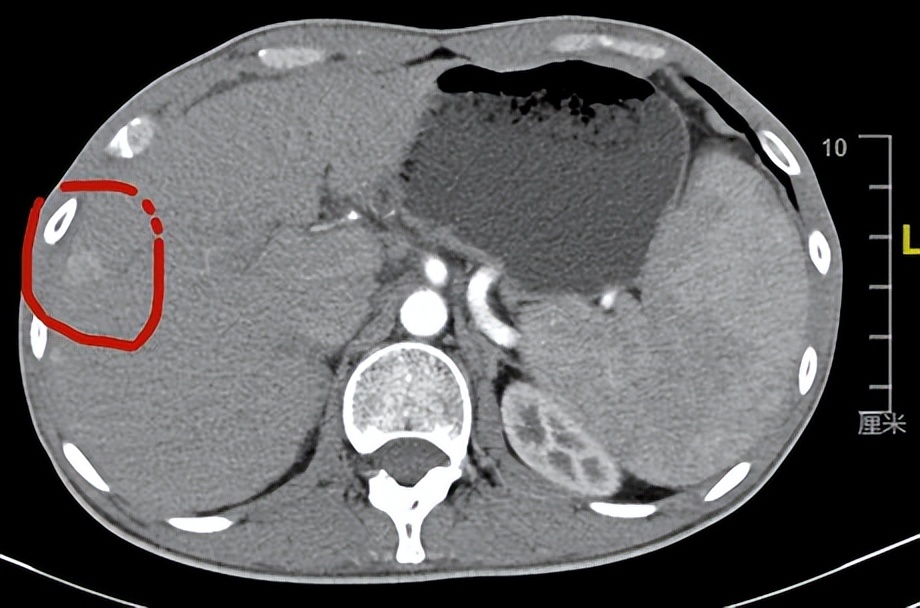

就这样耽误了半年,半年后出现了肝区疼痛,越来越重,这才想起来肝里有个小肿瘤,是不是要去复查下,到上海来就诊,复查了CT,结果出来也吓了我一跳,肿瘤已经涨到了10cm大小,并且侵犯血管,失去了手术机会。问他之前为什么不手术?家属看了病人一眼似乎有什么不好意思回答的原因,最后还是病人自己说了:因为害怕做完手术人就不能活了,好几个邻居都告诉他,身边某某某肿瘤开好刀没多久就走了,不治疗肯定人还在的之类的话。我又问他:你现在后悔吗?现在是真的不能手术了!病人还有点不相信,以为我还在骗他让他手术,接着问我:半年前可以,这么快就不能手术了?于是就给他解释了一通半年肿瘤会长大多少倍;为什么半年前可以手术,现在不能了;做手术和不做手术的利弊,做手术是治疗肝癌最有效的办法,如果手术都不能让你活下去,其它的办法更不行,等等说了很多!这次他听进去了,但却错失了可以根治肿瘤的最佳机会,实在可惜。

这个病人短短半年时间,肿瘤就从1.2厘米长到了10cm,肿瘤体积增大了10倍,从鸽子蛋大小变成了小西瓜大小,每2个月肿瘤体积会增大一倍,所以肝癌从1厘米长到10厘米,很多情况下只需要半年时间,这个速度真的还是很恐怖的,也能说明肝癌恶性程度的确高,生长速度快。当然并不是每个肝癌的生长速度都是这样的,有的人可能更快,也有的人很慢,但大多数肝癌的生长速度还是基本接近这个病人的状态。这也是为什么很多人一年前体检的时候好好的,但是再检查的时候就已经是肝癌晚期了。所以我要求乙肝携带者等肝癌高危人群,至少每半年复查一次肝脏彩超、肝功能、甲胎蛋白、异常凝血酶原,及早发现肝癌,争取根治性手术治疗!